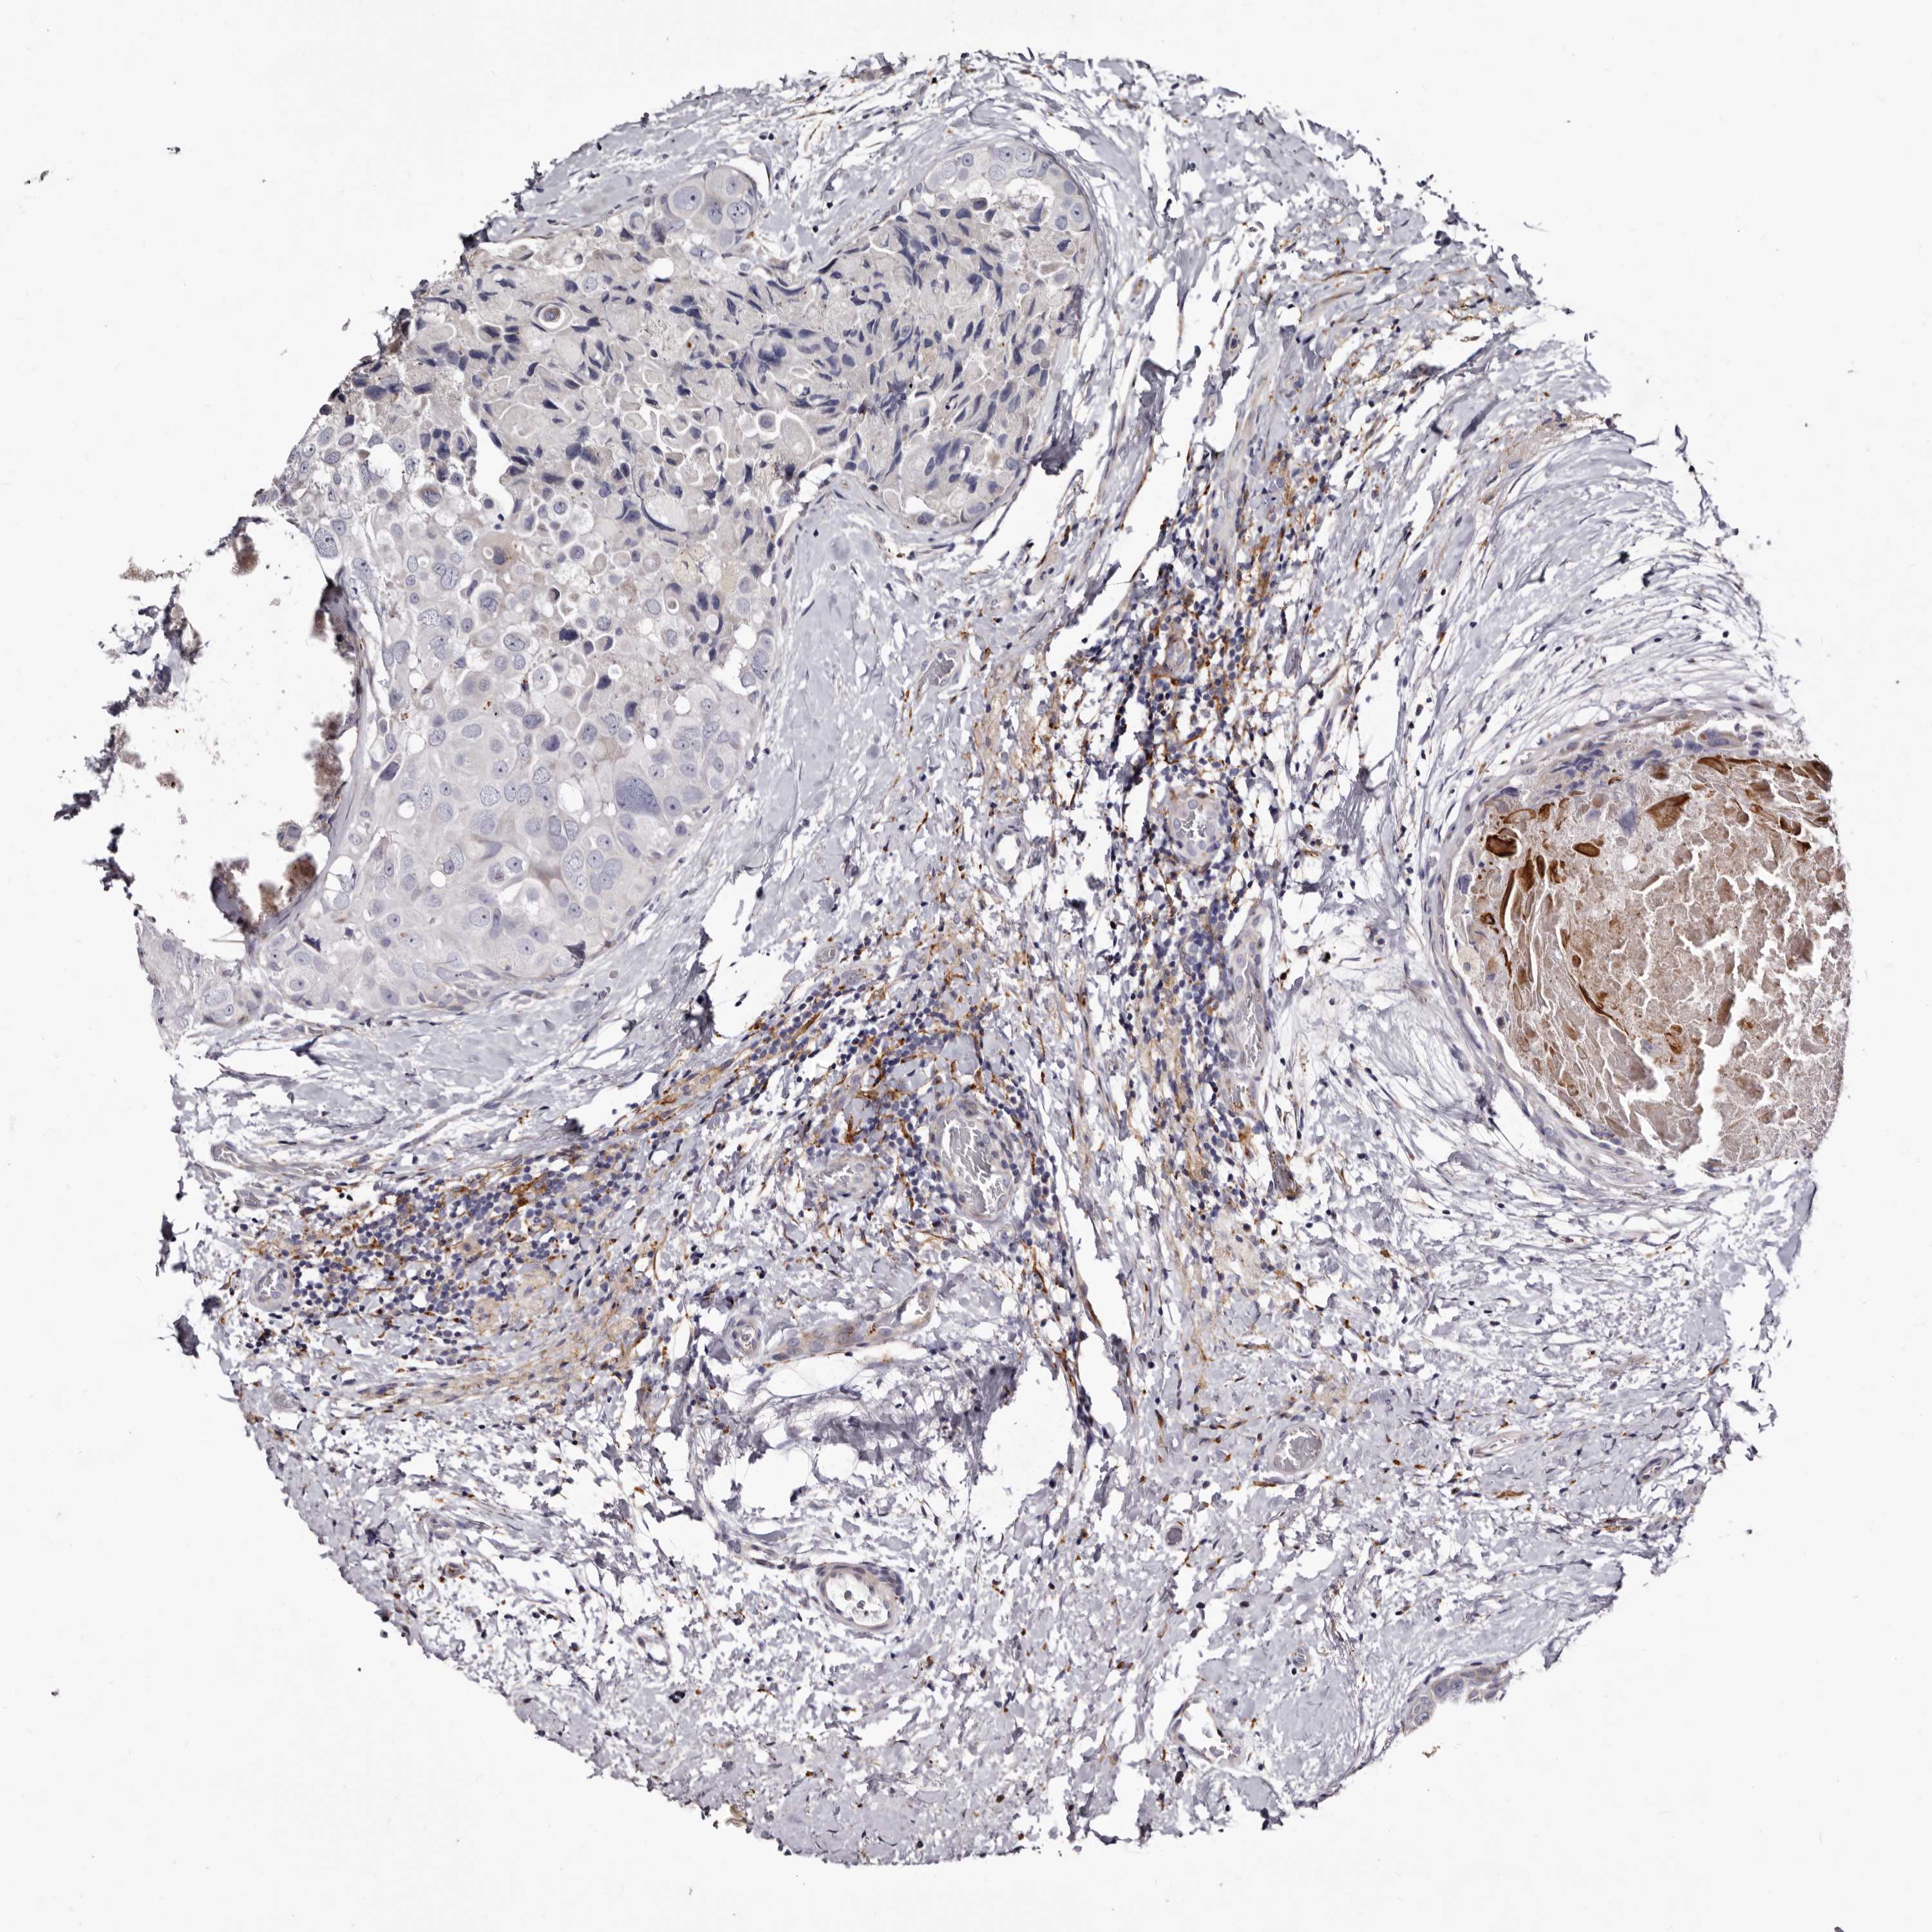

CANCER BREAST CANCER Show tissue menu

BRCA TCGA BRCA VALIDATION PROTEIN EXPRESSION

ANTIBODIES

AND

VALIDATION